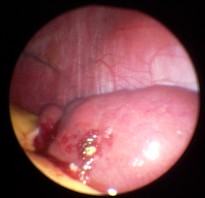

Milzbiopsie bei Sarkoidose